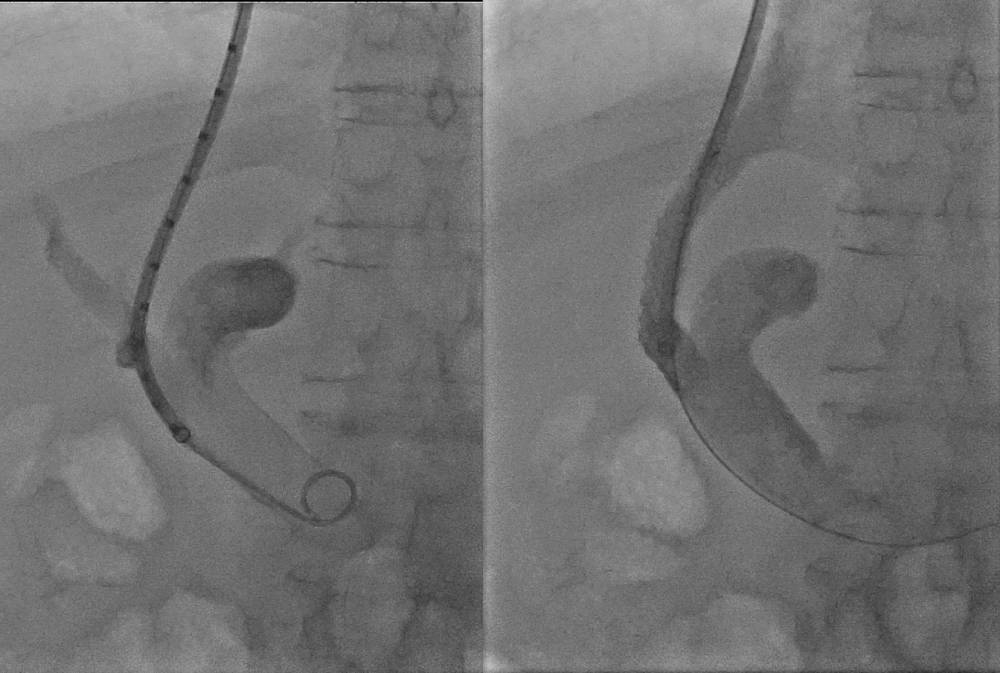

Patienten mit Leberzirrhose und zunehmender portaler Hypertension (Hochdruck im Darmvenensystem) profitieren unter bestimmten Umständen von der Anlage eines sog. Transjugulären Intrahepatischen Porto-systemischen Stent-Shunts (TIPS). Hierbei wird eine Gefäßprothese in einen völlig neuen Trakt durch das Leberparenchym platziert, um einen Pfortaderast mit einem Ast der Lebervene zu verbinden und durch den Blutfluss in diesem Shunt einen weitgehenden Druckausgleich mit Druckminderung im Portalsystem zu erzielen.

Es zeigt ein medizinisches Bild mit einem Katheter und einem Kontrastmittel in den Gelenken.